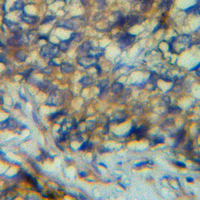

Immunohistochemical analysis of CCL8 staining in human adrenal gland formalin fixed paraffin embedded tissue section. The section was pre-treated using heat mediated antigen retrieval with sodium citrate buffer (pH 6.0). The section was then incubated with the antibody at room temperature and detected using an HRP conjugated compact polymer system. DAB was used as the chromogen. The section was then counterstained with haematoxylin and mounted with DPX.